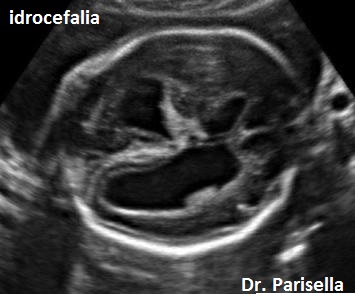

Le lesioni caratteristiche a carico del SNC sono rappresentate  da idrocefalo grave, con ventricoli aperti nello spazio subaracnoideo, ipoplasia cerebrale, anomalie della linea mediana e del setto pellucido (agenesia del corpo calloso); possono essere presenti encefalocele occipitale, una caratteristica conformazione del forame magno “key-hole shaped”, mandibola piccola e naso malformato, labio-palatoschisi. Caratteristica è la polidattilia postassiale alle mani e preassiale ai piedi (l'alluce duplice è altamente caratteristico, quasi esclusivo, di questa condizione morbosa). Segnalati anche piede torto e difetti cardiovascolari (difetti del setto atriale; atrio unico). Come ha segnalato lo studio di Salonen e coll. (1981) condotto su 28 neonati di 18 famiglie, l'esito abituale della gravidanza è la nascita di feto morto o morte in epoca neonatale.

La Diagnosi Prenatale si basa su: 1) assenza di movimenti attivi fetali; 2) polidattilia postassiale alle mani; 3) polidattilia preassiale ai piedi;  4) idrocefalia; 5) polidramnios.